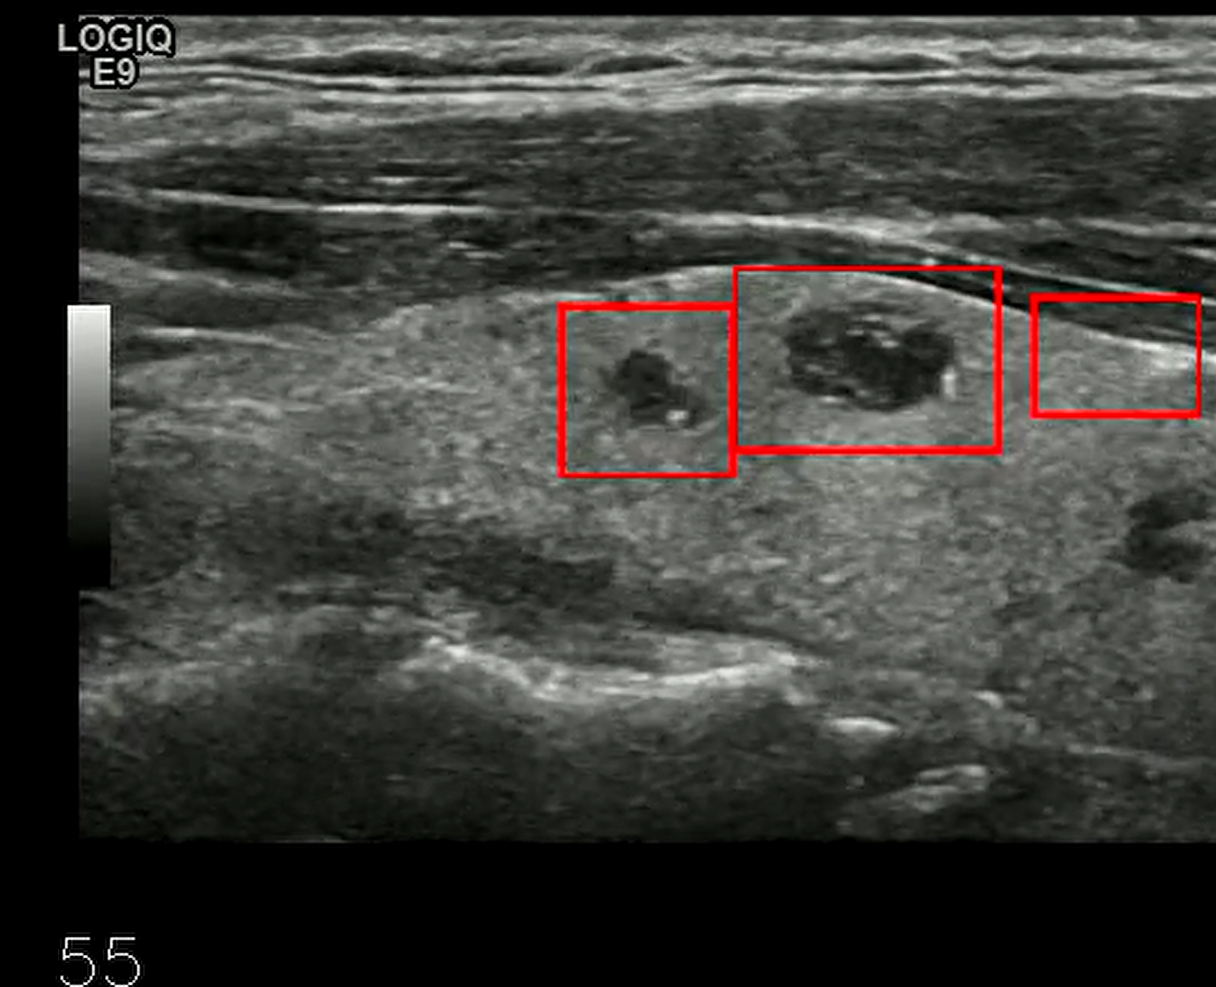

处理后: